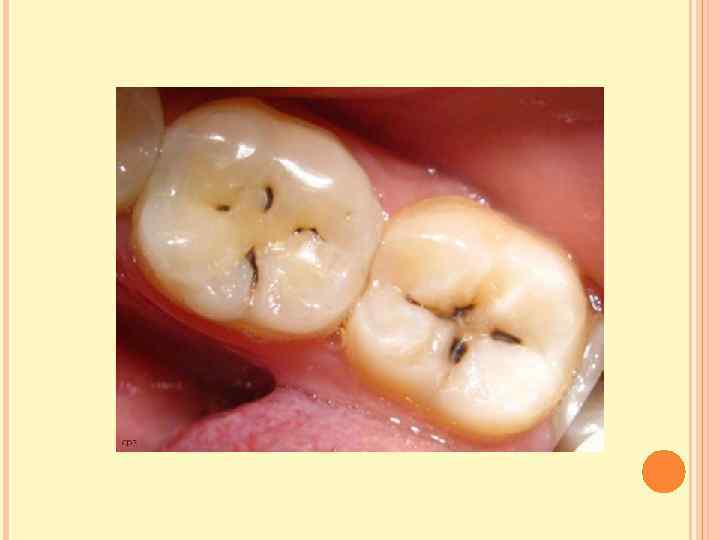

КЛИНИЧЕСКАЯ КАРТИНА. СРЕДНИЙ КАРИЕС. При этой форме кариозного процесса целостность эмалеводентинного соединения нарушается, однако под полостью зуба сохраняется достаточно толстый слой дентина. Жалобы: могут не предъявлять, но иногда боль возникает от воздействия механических, химических, термических раздражителей, которые быстро проходят после устранения раздражителя. Осмотр: неглубокая кариозная полость, заполненная размягчённым, пигментированным дентином, что определяется при зондировании. При наличии размягчённого дентина в фиссуре зонд задерживается, застревает в ней. При хроническом течении кариеса при зондировании выявляется плотное дно и стенки полости, широкое входное отверстие. При остротекущей форме кариеса – обилие размягчённого дентина на стенках и дне полости, подрытые, острые и хрупкие края. Зондирование болезненно по эмалеводентинному соединению. Пульпа зуба реагирует на силу тока 2 -6 мк. А.

КЛИНИЧЕСКАЯ КАРТИНА. СРЕДНИЙ КАРИЕС. При этой форме кариозного процесса целостность эмалеводентинного соединения нарушается, однако под полостью зуба сохраняется достаточно толстый слой дентина. Жалобы: могут не предъявлять, но иногда боль возникает от воздействия механических, химических, термических раздражителей, которые быстро проходят после устранения раздражителя. Осмотр: неглубокая кариозная полость, заполненная размягчённым, пигментированным дентином, что определяется при зондировании. При наличии размягчённого дентина в фиссуре зонд задерживается, застревает в ней. При хроническом течении кариеса при зондировании выявляется плотное дно и стенки полости, широкое входное отверстие. При остротекущей форме кариеса – обилие размягчённого дентина на стенках и дне полости, подрытые, острые и хрупкие края. Зондирование болезненно по эмалеводентинному соединению. Пульпа зуба реагирует на силу тока 2 -6 мк. А.